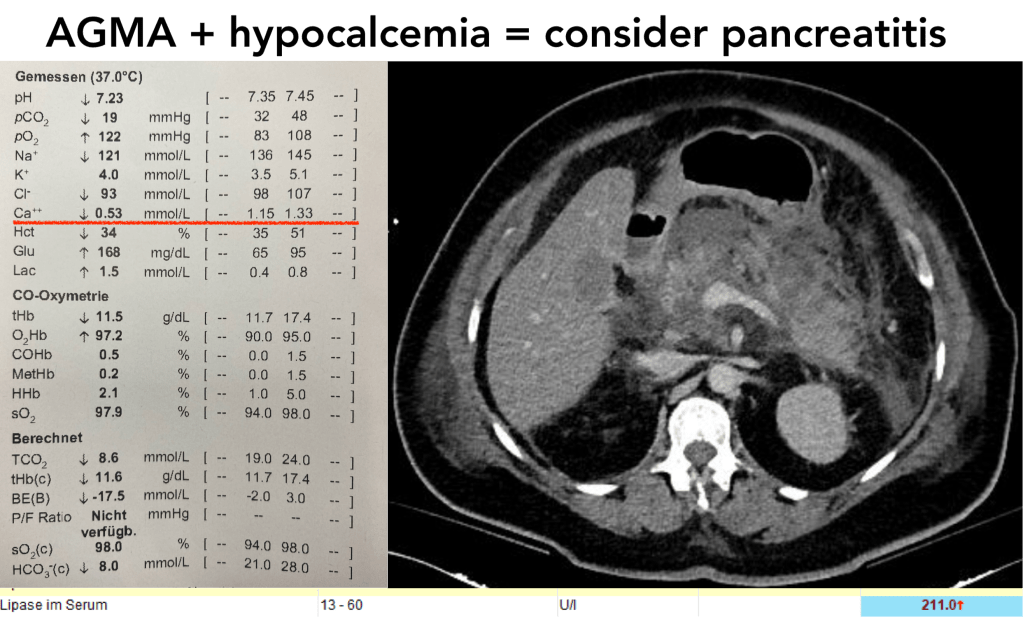

metabolic acidosis: presentation of data